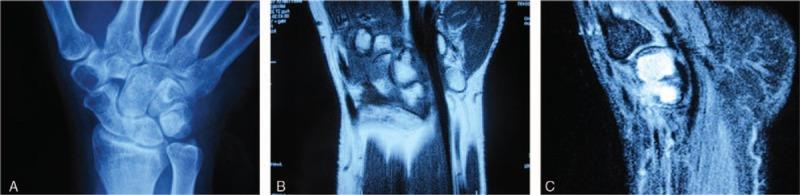

Fibroma of tendon sheath embedded in carpal bones mimicking carpal enchondroma: A case report.

Fibroma embedded into carpal bones, which exhibited lytic radiographic features similar to those of enchondroma. Excisional biopsy demonstrated spindle-shaped cells and collagen-like stroma.

This case provides valuable insights for hand surgeons. While radiograph is helpful in multiple diseases, histological examination is indispensable for establishment of final diagnosis.